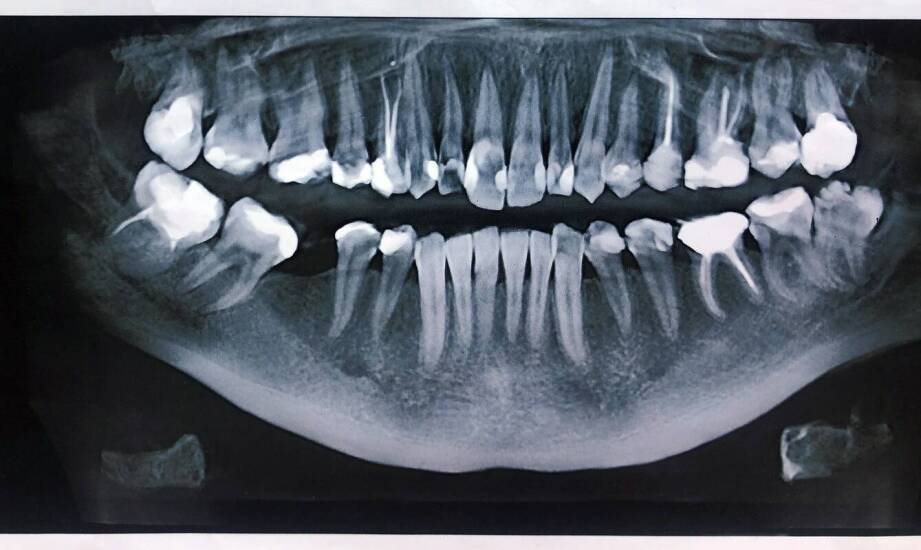

CBCT, czyli tomografia stożkowa, wykonuje serię rotacyjnych zdjęć głowy i składa je w dokładny model 3D. W odróżnieniu od zwykłego RTG panoramicznego, CBCT pokazuje struktury bez nakładania się obrazów, a więc widać kanały, korzenie, przebieg nerwów oraz jakość kości z dużą szczegółowością.

Diagnostyka endodontyczna: w leczeniu kanałowym kluczowe jest odnalezienie wszystkich kanałów, wykrycie złamań korzeni, perforacji i zmian okołowierzchołkowych niewidocznych na klasycznych zdjęciach. CBCT pokazuje prawdziwą anatomię zęba i pozwala na celowane, mniej inwazyjne leczenie.

Diagnostyka poekstrakcyjna i urazowa: po usunięciu zęba CBCT ocenia gojenie, obecność resztek korzeni, ewentualne perforacje dna zatoki. Po urazach ujawnia pęknięcia szkliwa i zębiny, złamania korzeni czy wyrostka zębodołowego.